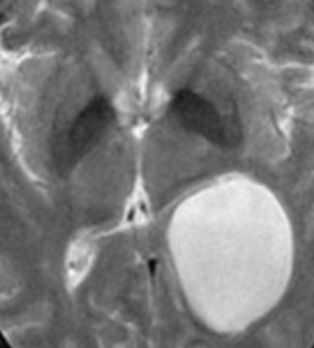

Пинеальная киста расположена в проекции шишковидной железы. Встречается с частотой 4-11%. Размеры обычно не превышают 1 см, но изредка встречаются больших размеров. В таких случаях она вызывает окклюзионную гидроцефалию. При головного мозга она имеет все признаки кисты с примесью белка в жидкости, то есть немного светлая на Т1-взвешенных. Изредка встречается геморрагическое содержимое. Киста может контрастироваться по периферии.

Пинеальная киста расположена в проекции шишковидной железы. Встречается с частотой 4-11%. Размеры обычно не превышают 1 см, но изредка встречаются больших размеров. В таких случаях она вызывает окклюзионную гидроцефалию. При МРТ головного мозга она имеет все признаки кисты с примесью белка в жидкости, то есть немного светлая на Т1-зависимых МРТ. Изредка встречается геморрагическое содержимое. Киста может по усиливаться периферии при МРТ головного мозга с контрастированием.